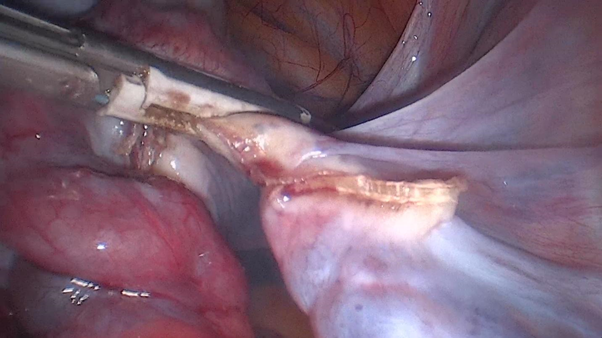

Intraoperative images

1. The right ureter is located and the right infundibulopelvic ligament is sectioned with advanced bipolar energy.

1. Right salpingo-oophorectomy is performed.